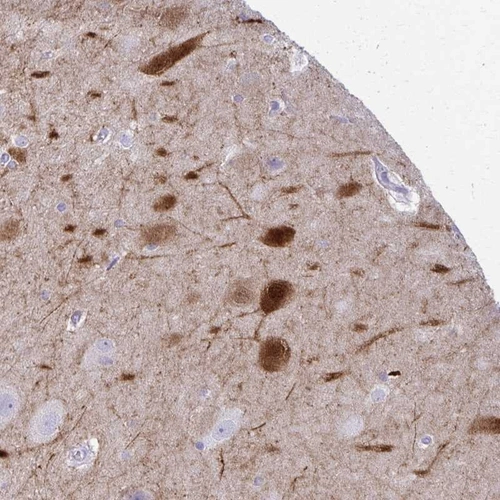

Immunohistochemical staining of human hippocampus shows strong cytoplasmic and nuclear positivity in neuronal cells.